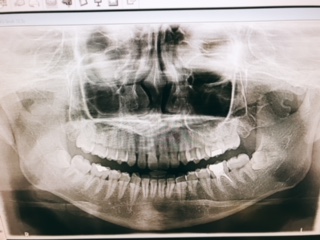

抜歯、、、怖いな、、、。と思いましたがその影響で

手前の健康な歯が悪くなってしまうのは絶対に避けたいと思い

抜歯してもらう事にしました。

今回、診断してもらい、やはり違和感や痛みを少しでも感じたら

放置せずに先生に診てもらったほうが良いな〜・・・

と改めて思いました。

まさか隣の親知らずが原因!

とは全く思ってもいなかったので。。。。